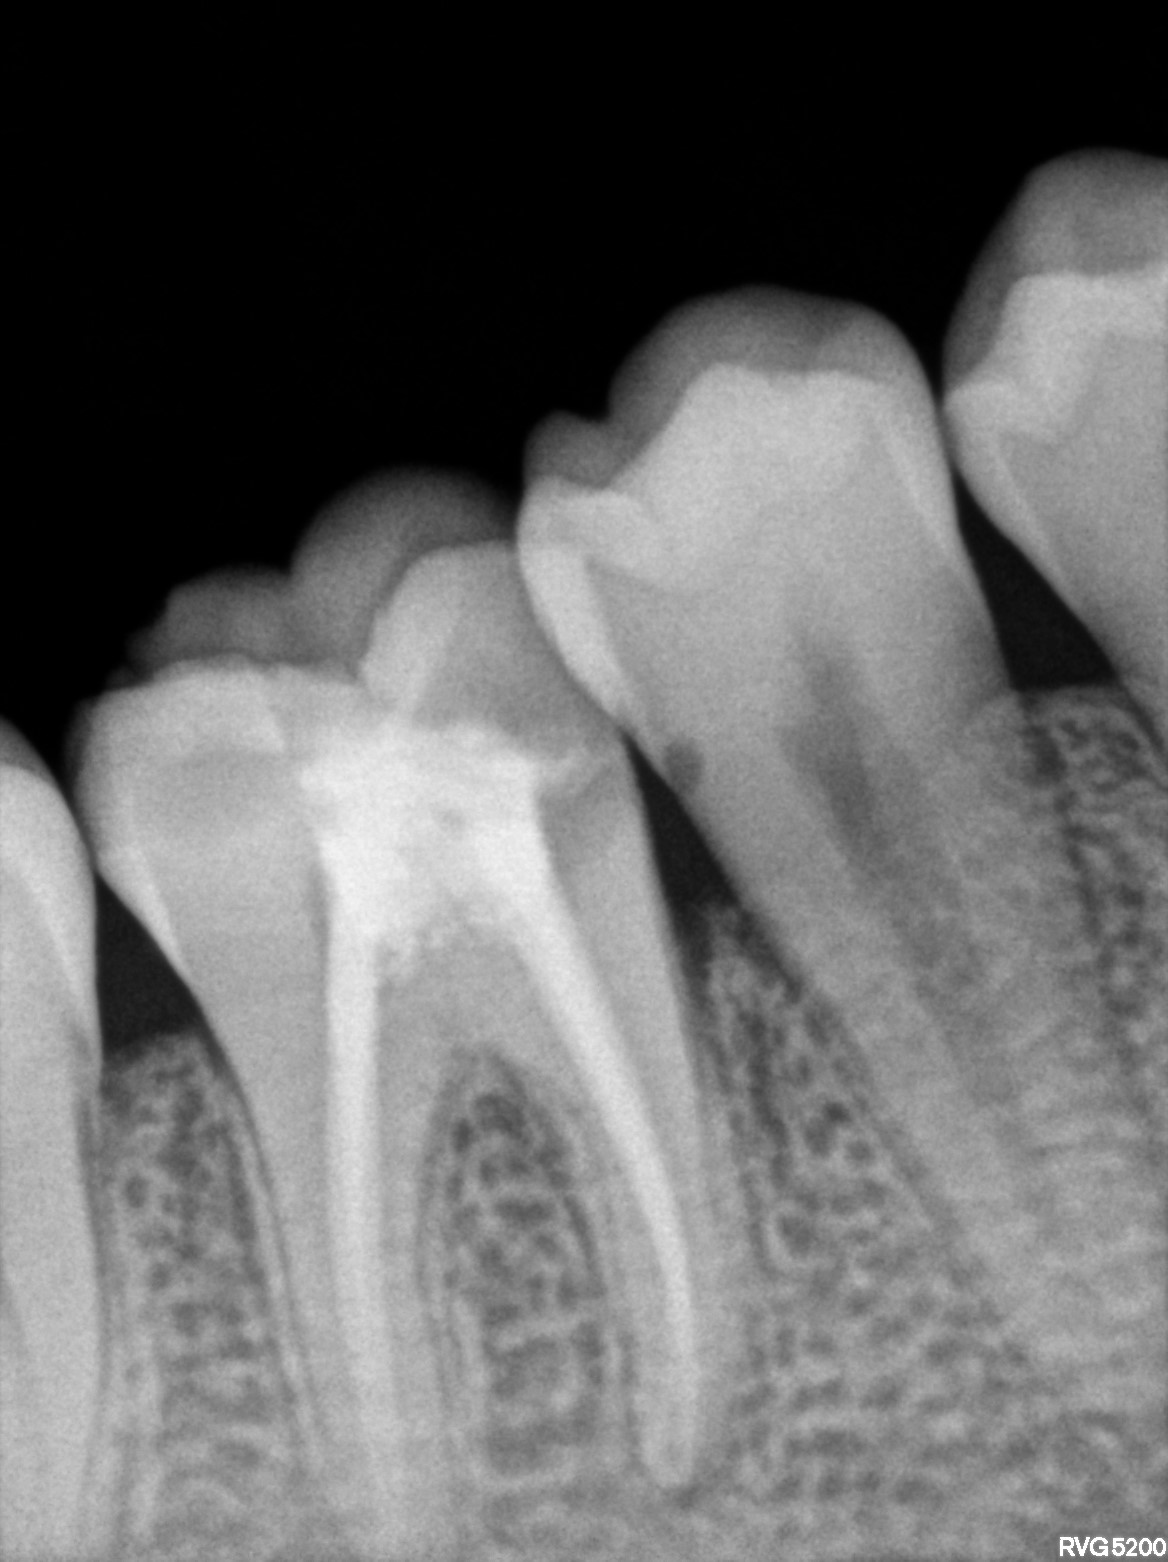

Dental Radiographs FHIR: DocumentReference · LOINC 24641-7

R61.jpg

24641-7

R67.jpg